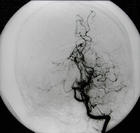

烟雾病又名脑底异常血管网,是一组以颈内动脉虹吸部及大脑前、中动脉起始部狭窄或闭塞,脑底出现异

常的小血管网为特点的脑血管病。因脑血管造影时呈现许多密集成堆的小血管影,似吸烟时吐出的烟雾,故名烟雾病。

脑血管造影可以发现颈内动脉起始部、大脑前、中动脉起始段狭窄或不显影,基底节区可见大量细小血管团如吸烟吐出的烟雾。此外可见脑内形成侧支循环代偿支。随着病程的延长,代偿吻合支的数量逐渐减少或缩小。

5.脑血管造影 见颈内动脉虹吸上段和大脑前、中动脉起始部狭窄,脑底烟雾状异常血管网和广泛的侧支循环形成。应与脑动脉硬化性脑梗死和动静脉畸形鉴别。